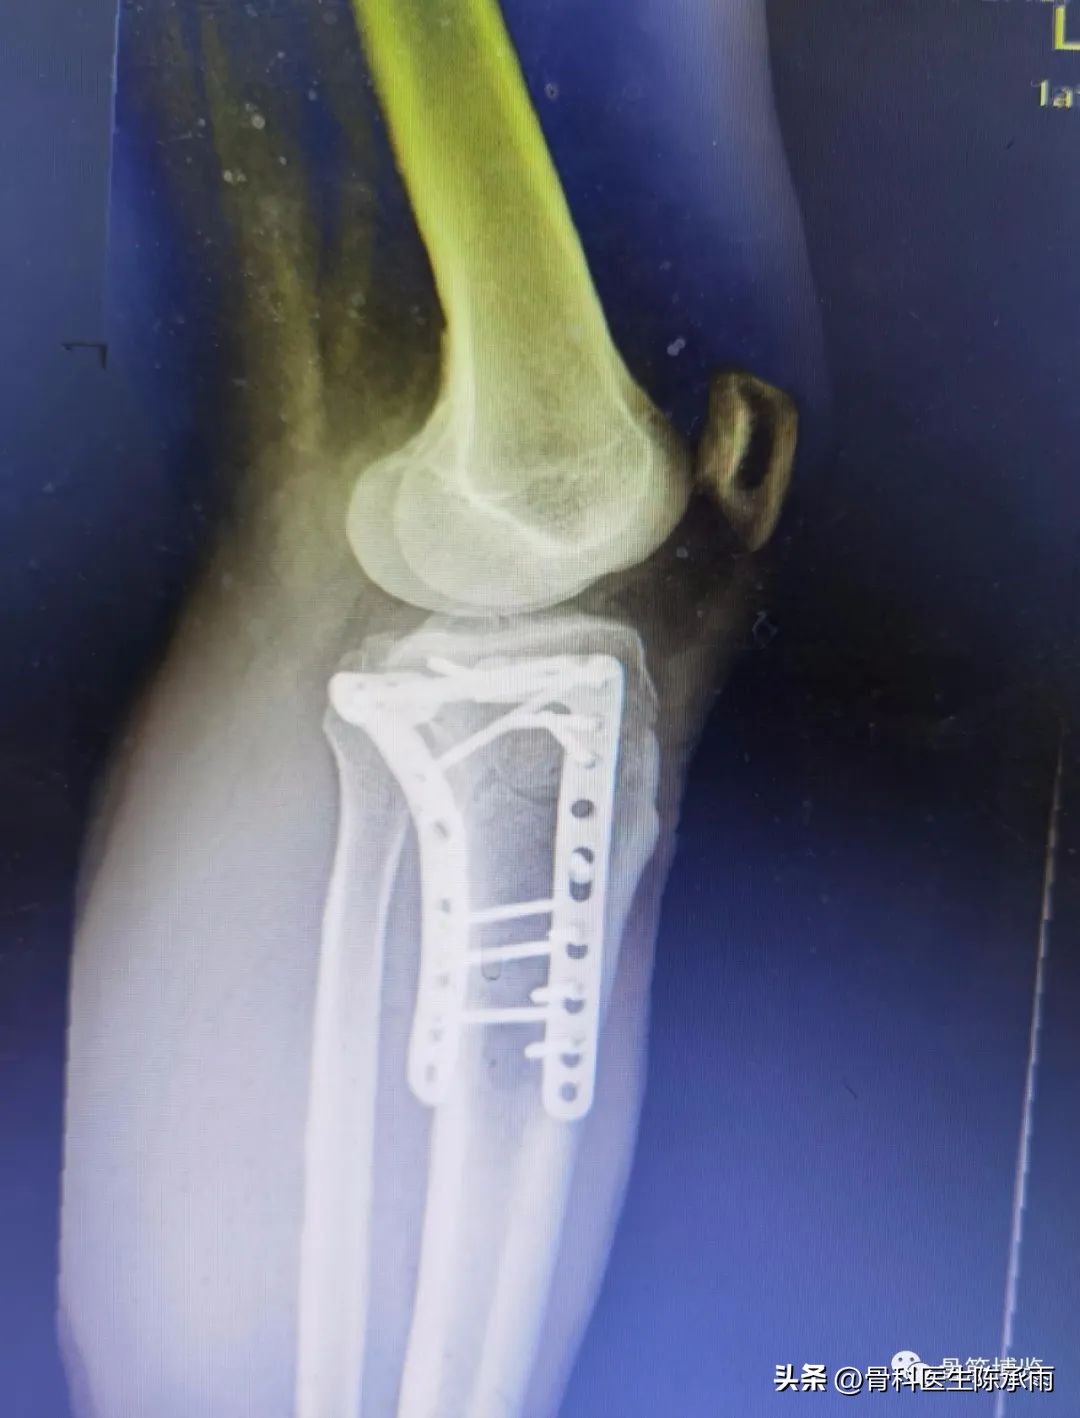

1例

2例

3例

4例

5例

6例

7例